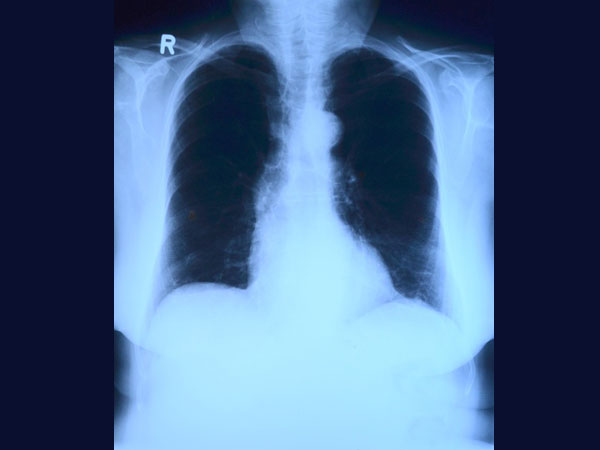

Mohammed Maqsood was rushed to the hospital on November 18th, after he complained of a terrible stomach ache. The cause of his stomach pain was identified through an X-ray, but the doctors were literally shocked to remove metal coins and other things from his stomach during the operation.

Almost 6 expert doctors were engaged in removing these objects from Mohammed Maqsood's stomach. The team of doctors removed items weighing close of 5 kg. The items surgically removed from the patients' stomach included 4 big needles, a chain, 263 coins, 10-12 shaving blades and some pieces of glass. The doctor said that this case was shocking and it was the first time when he has seen something like this in his career. One of the doctors said, "The operation was done in the nick of the time as some of the nails lodged had pierced his stomach, caused bleeding and resulting in loss of hemoglobin."